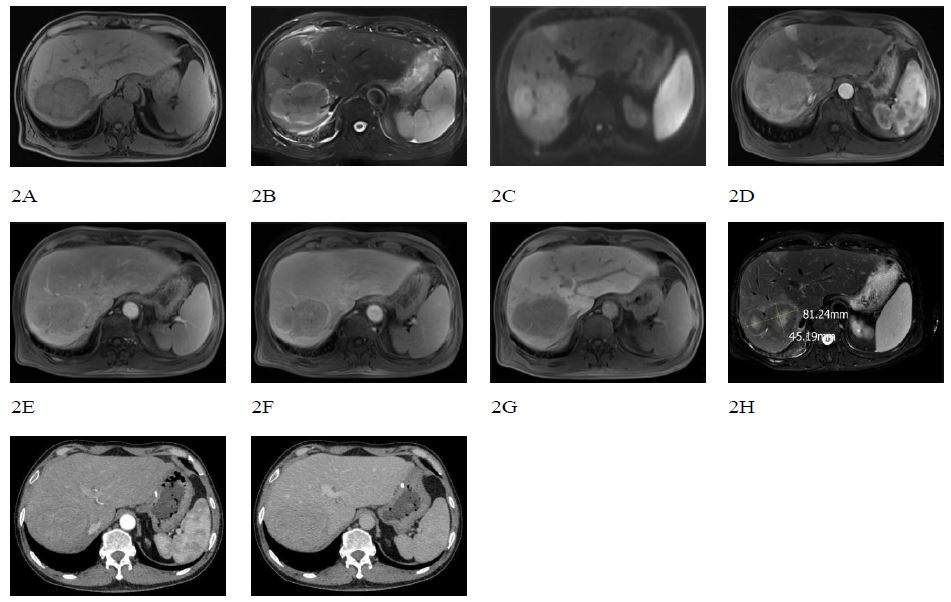

A 56-year-old male patient was admitted to the hospital due to persistent fatigue and shortness of breath lasting for more than 2 months. An ultrasound (Figure 1) performed at an external facility revealed a hepatic shadow that has not improved despite treatment. On April 12, 2017, the patient underwent pancreaticoduodenectomy followed by intraperitoneal chemical particle implantation for the treatment of a pancreatic cyst associated with chronic pancreatitis. Laboratory tests revealed elevated levels of C-reactive protein and abnormal liver function. AFP (-), CEA (-). MRI of the abdomen (Figure 2A-G) showed a large mass measuring approximately 81×61 mm in the right posterior lobe of the liver, characterized by a “double-ring” appearance at the edge. The mass exhibited low signal intensity on T1WI, slightly high signal on T2WI, mild diffusion restriction on DWI, inhomogeneous enhancement on the arterial phase, decreased enhancement in both the venous and delayed phases, and low uptake on the hepatobiliary phase. Localized intrahepatic bile duct invasion within the right lobe of the liver, accompanied by distal dilatation, edema, and abnormal perfusion of the surrounding liver tissue. MRI findings suggest a possible infectious liver lesion, and the tumor could not be drained. Pathological sections of the biopsy obtained from the local hospital consultation (Figure 3) showed fibrous tissue hyperplasia, foam-like histiocyte aggregates observed under the microscope, small spherical fungi with a powder-stained appearance in the cytoplasm, significant neutrophilic infiltration in the interstitium, and filamentous mycobacterial clusters visible at the tissue edge. Rabbit immunohistochemistry of tissue block B showed positive staining for CK (Pan) in residual hepatocytes and for CD68 in histiocytes. Special stains performed on tissue block B revealed reticular scaffold breaks on Masson staining, reticular fibers, positive staining with PAS, and silver stains. The pathological diagnosis of the liver tissue demonstrated morphology consistent with Actinomyces infection, with special staining suggesting a concomitant Cryptococcal infection.

Figure 1: Image of ultrasound revealed a hepatic shadow.